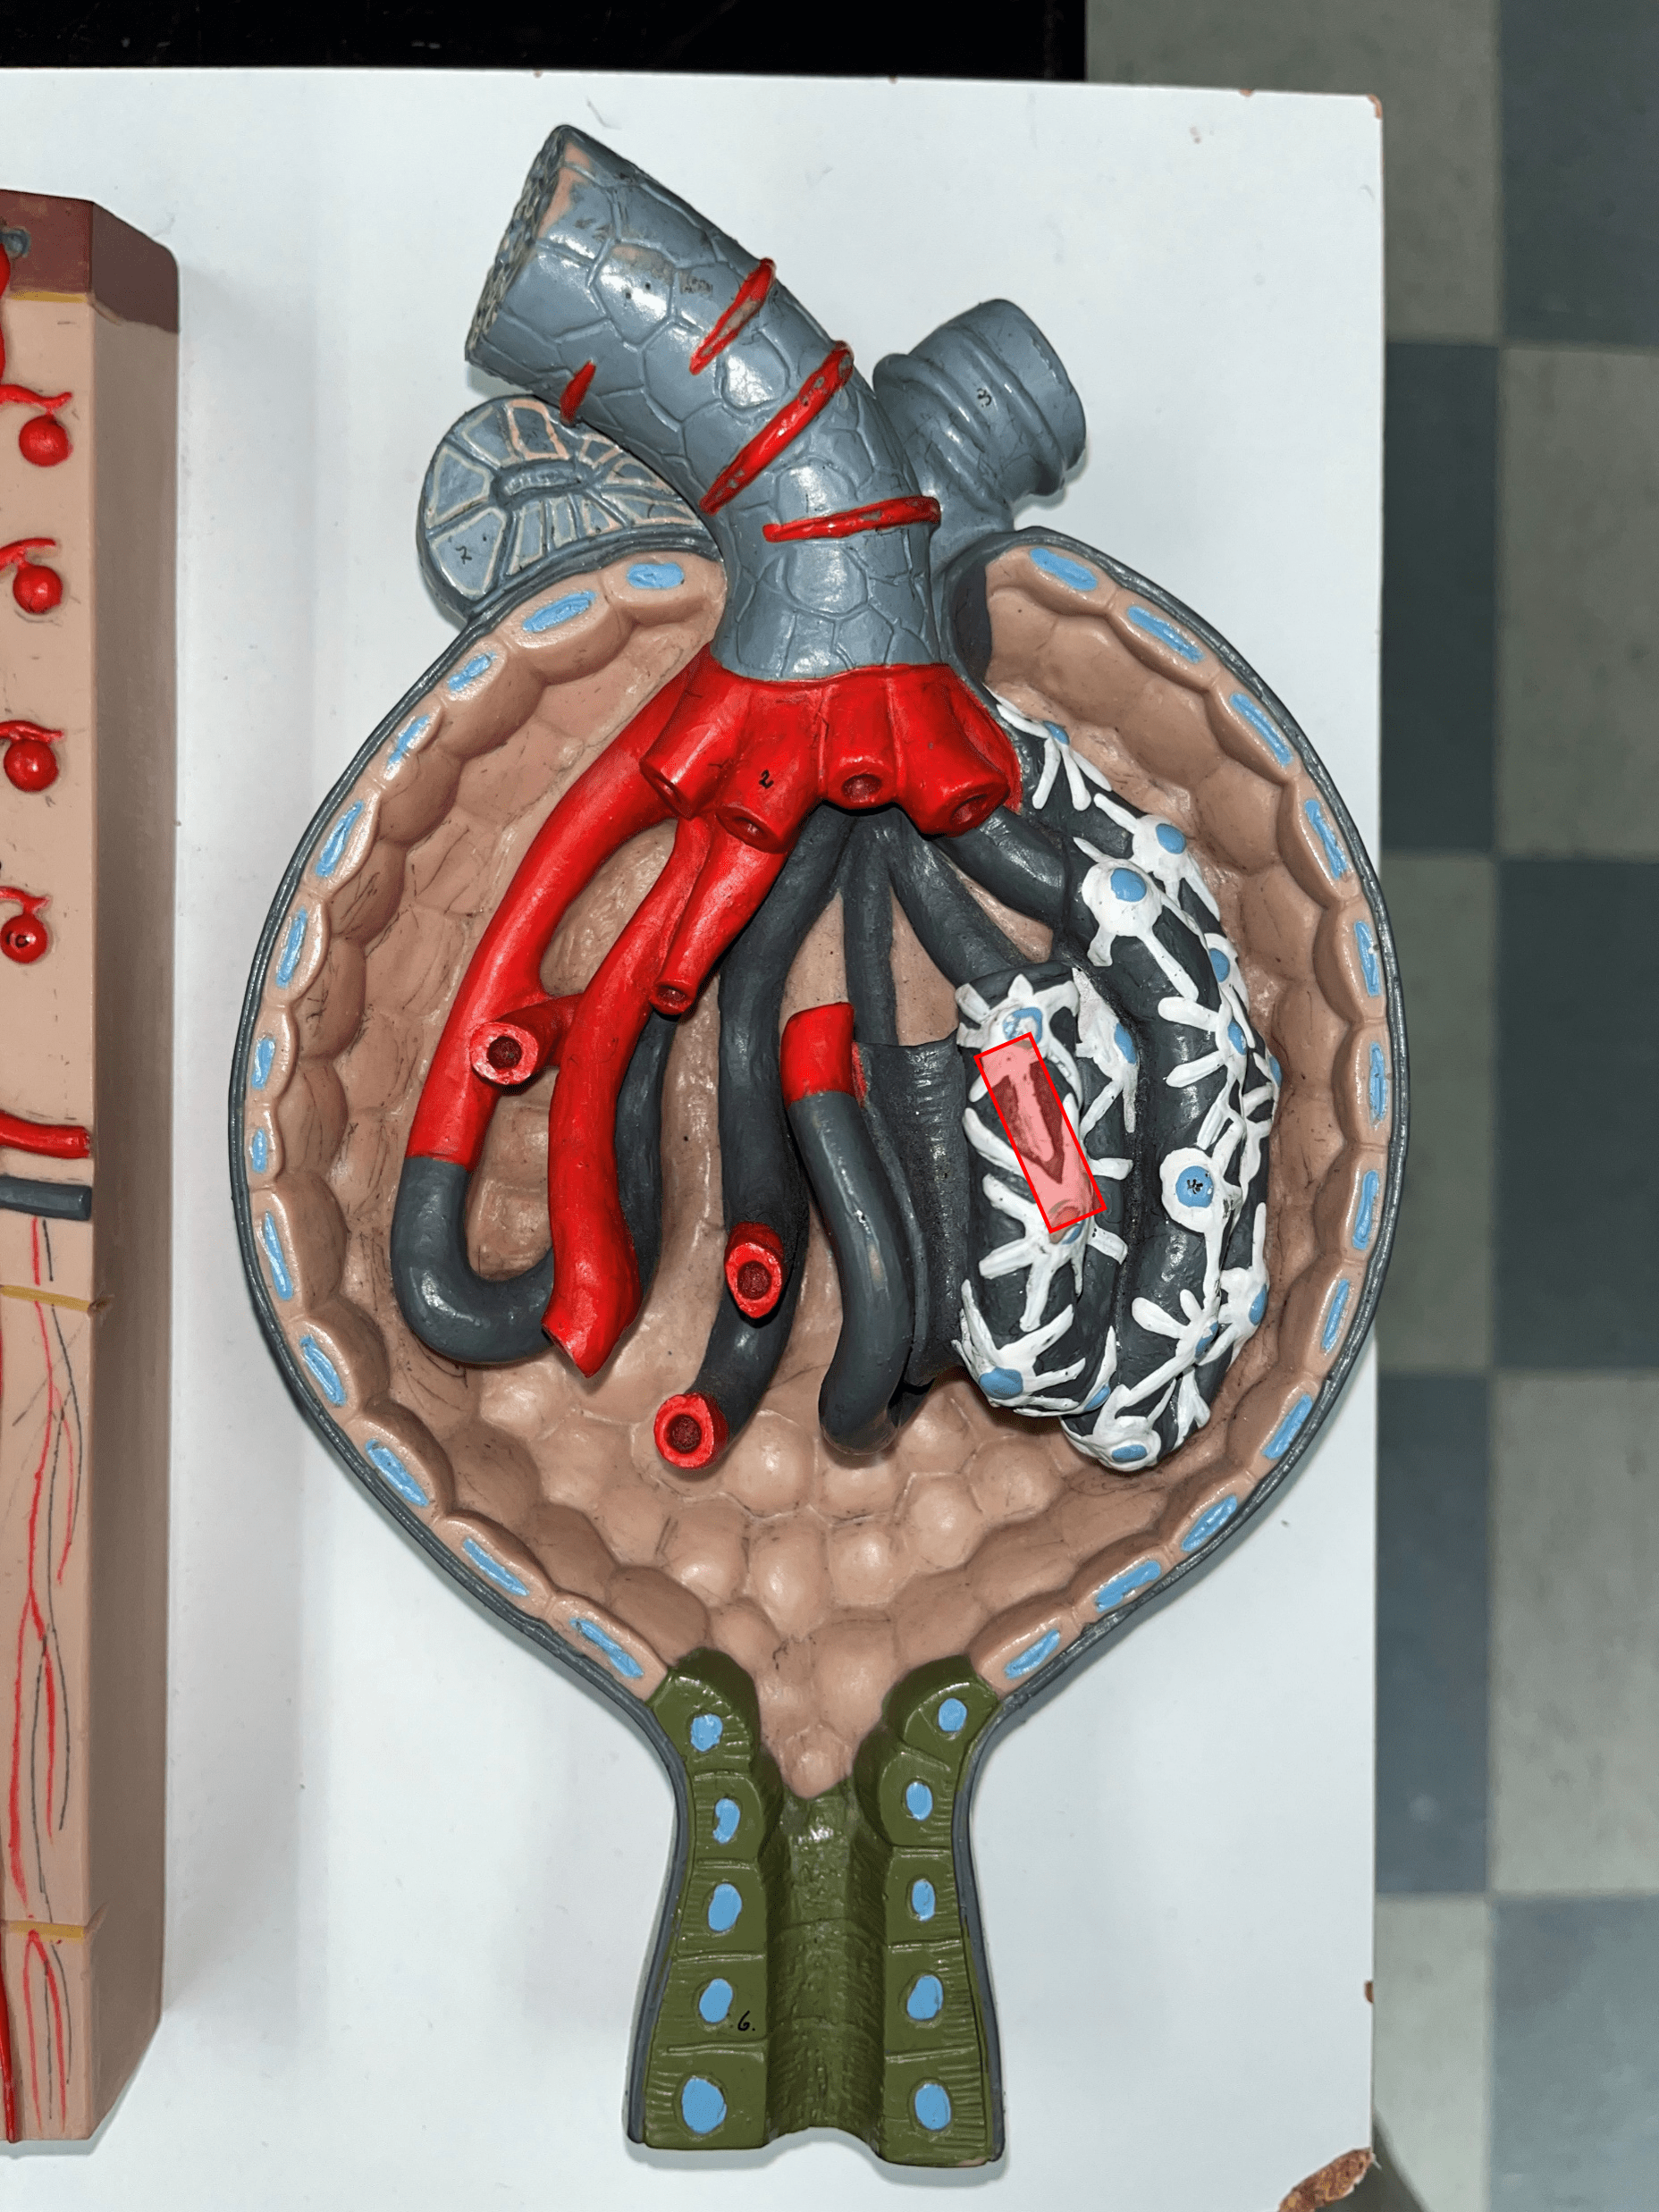

minor calyx

• A cup-like extension that collect urine from the renal papilla.

• Converges with others to form a larger major calyx.

• Converges with others to form a larger major calyx.

major calyx

• The convergence of several minor calyces.

• Drains into the renal pelvis.

• Drains into the renal pelvis.

renal pelvis

• The innermost region of the internal kidney.

• Collects urine from the major calyces and drains it into the ureters.

• Includes the minor and major calyces.

• Collects urine from the major calyces and drains it into the ureters.

• Includes the minor and major calyces.